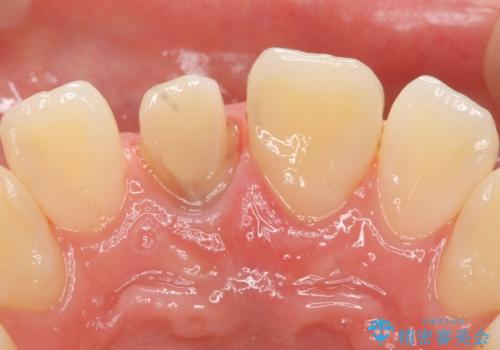

- 右上1番目の前歯の変色が気になるといらっしゃった方の症例です。

再根管治療後、オールセラミッククラウンによる補綴を行いました。

今回用いたオールセラミッククラウンはジルコニアフレームという白い素材の上にセラミックを盛っているため、審美性が非常に高いのが特徴です。

また、ジルコニアは人工ダイヤモンドの材料にも使われているほど高い強度を持っており、そのためオールセラミッククラウンは審美性だけでなく、奥歯やブリッジの補綴も可能とするクラウンです。